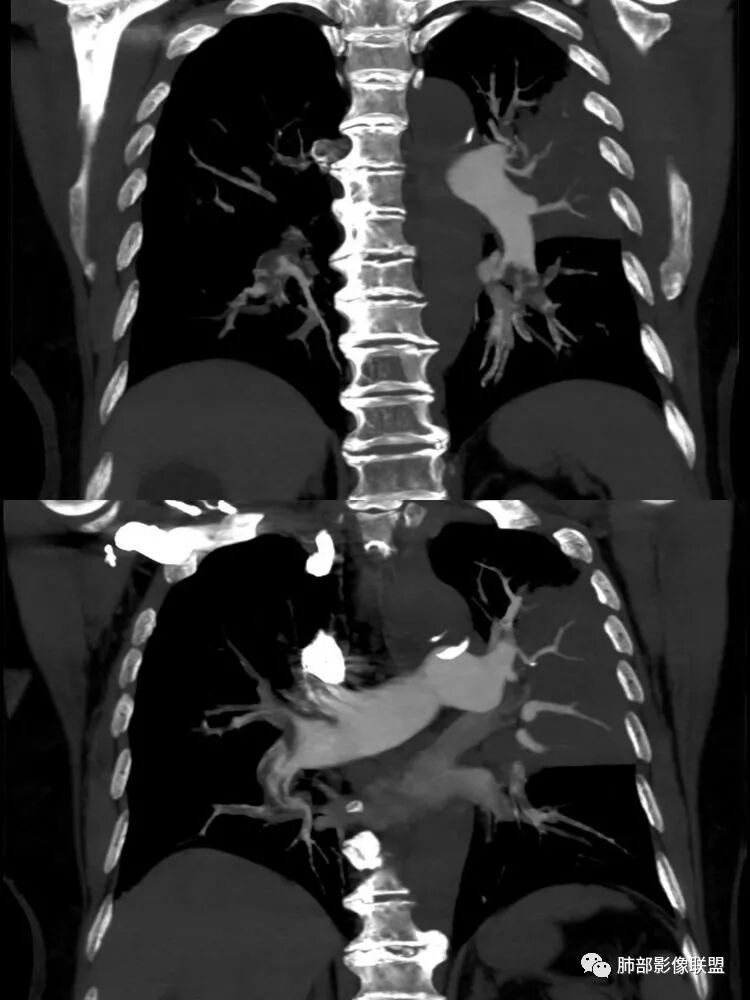

南边:这个是左上肺基本没啥功能所致吧肺动脉粗了尘缘:晨读:一、肺栓,CTPA去证实,这个一定有的,二,结核?这个不一定是,也不一定有结果,3、间质性肺水肿,这个应该有,但结果不一定能体现出来。综上:考虑肺栓塞伴间质性肺水肿,结核待排。

影像特点支持结核。气促、左上肺病灶似乎不能解释I型呼吸衰竭加上D—二聚体明显升高、肺动脉干增粗,临床需要想到二元可能:肺结核合并肺栓塞可能,需要完善CTPA明确有没有肺栓塞,因为急性肺栓塞是急危重症。

2.纵隔左移。肺动脉增宽。

D-二聚体升高,肺动脉成像等明确患者肺栓塞的存在!